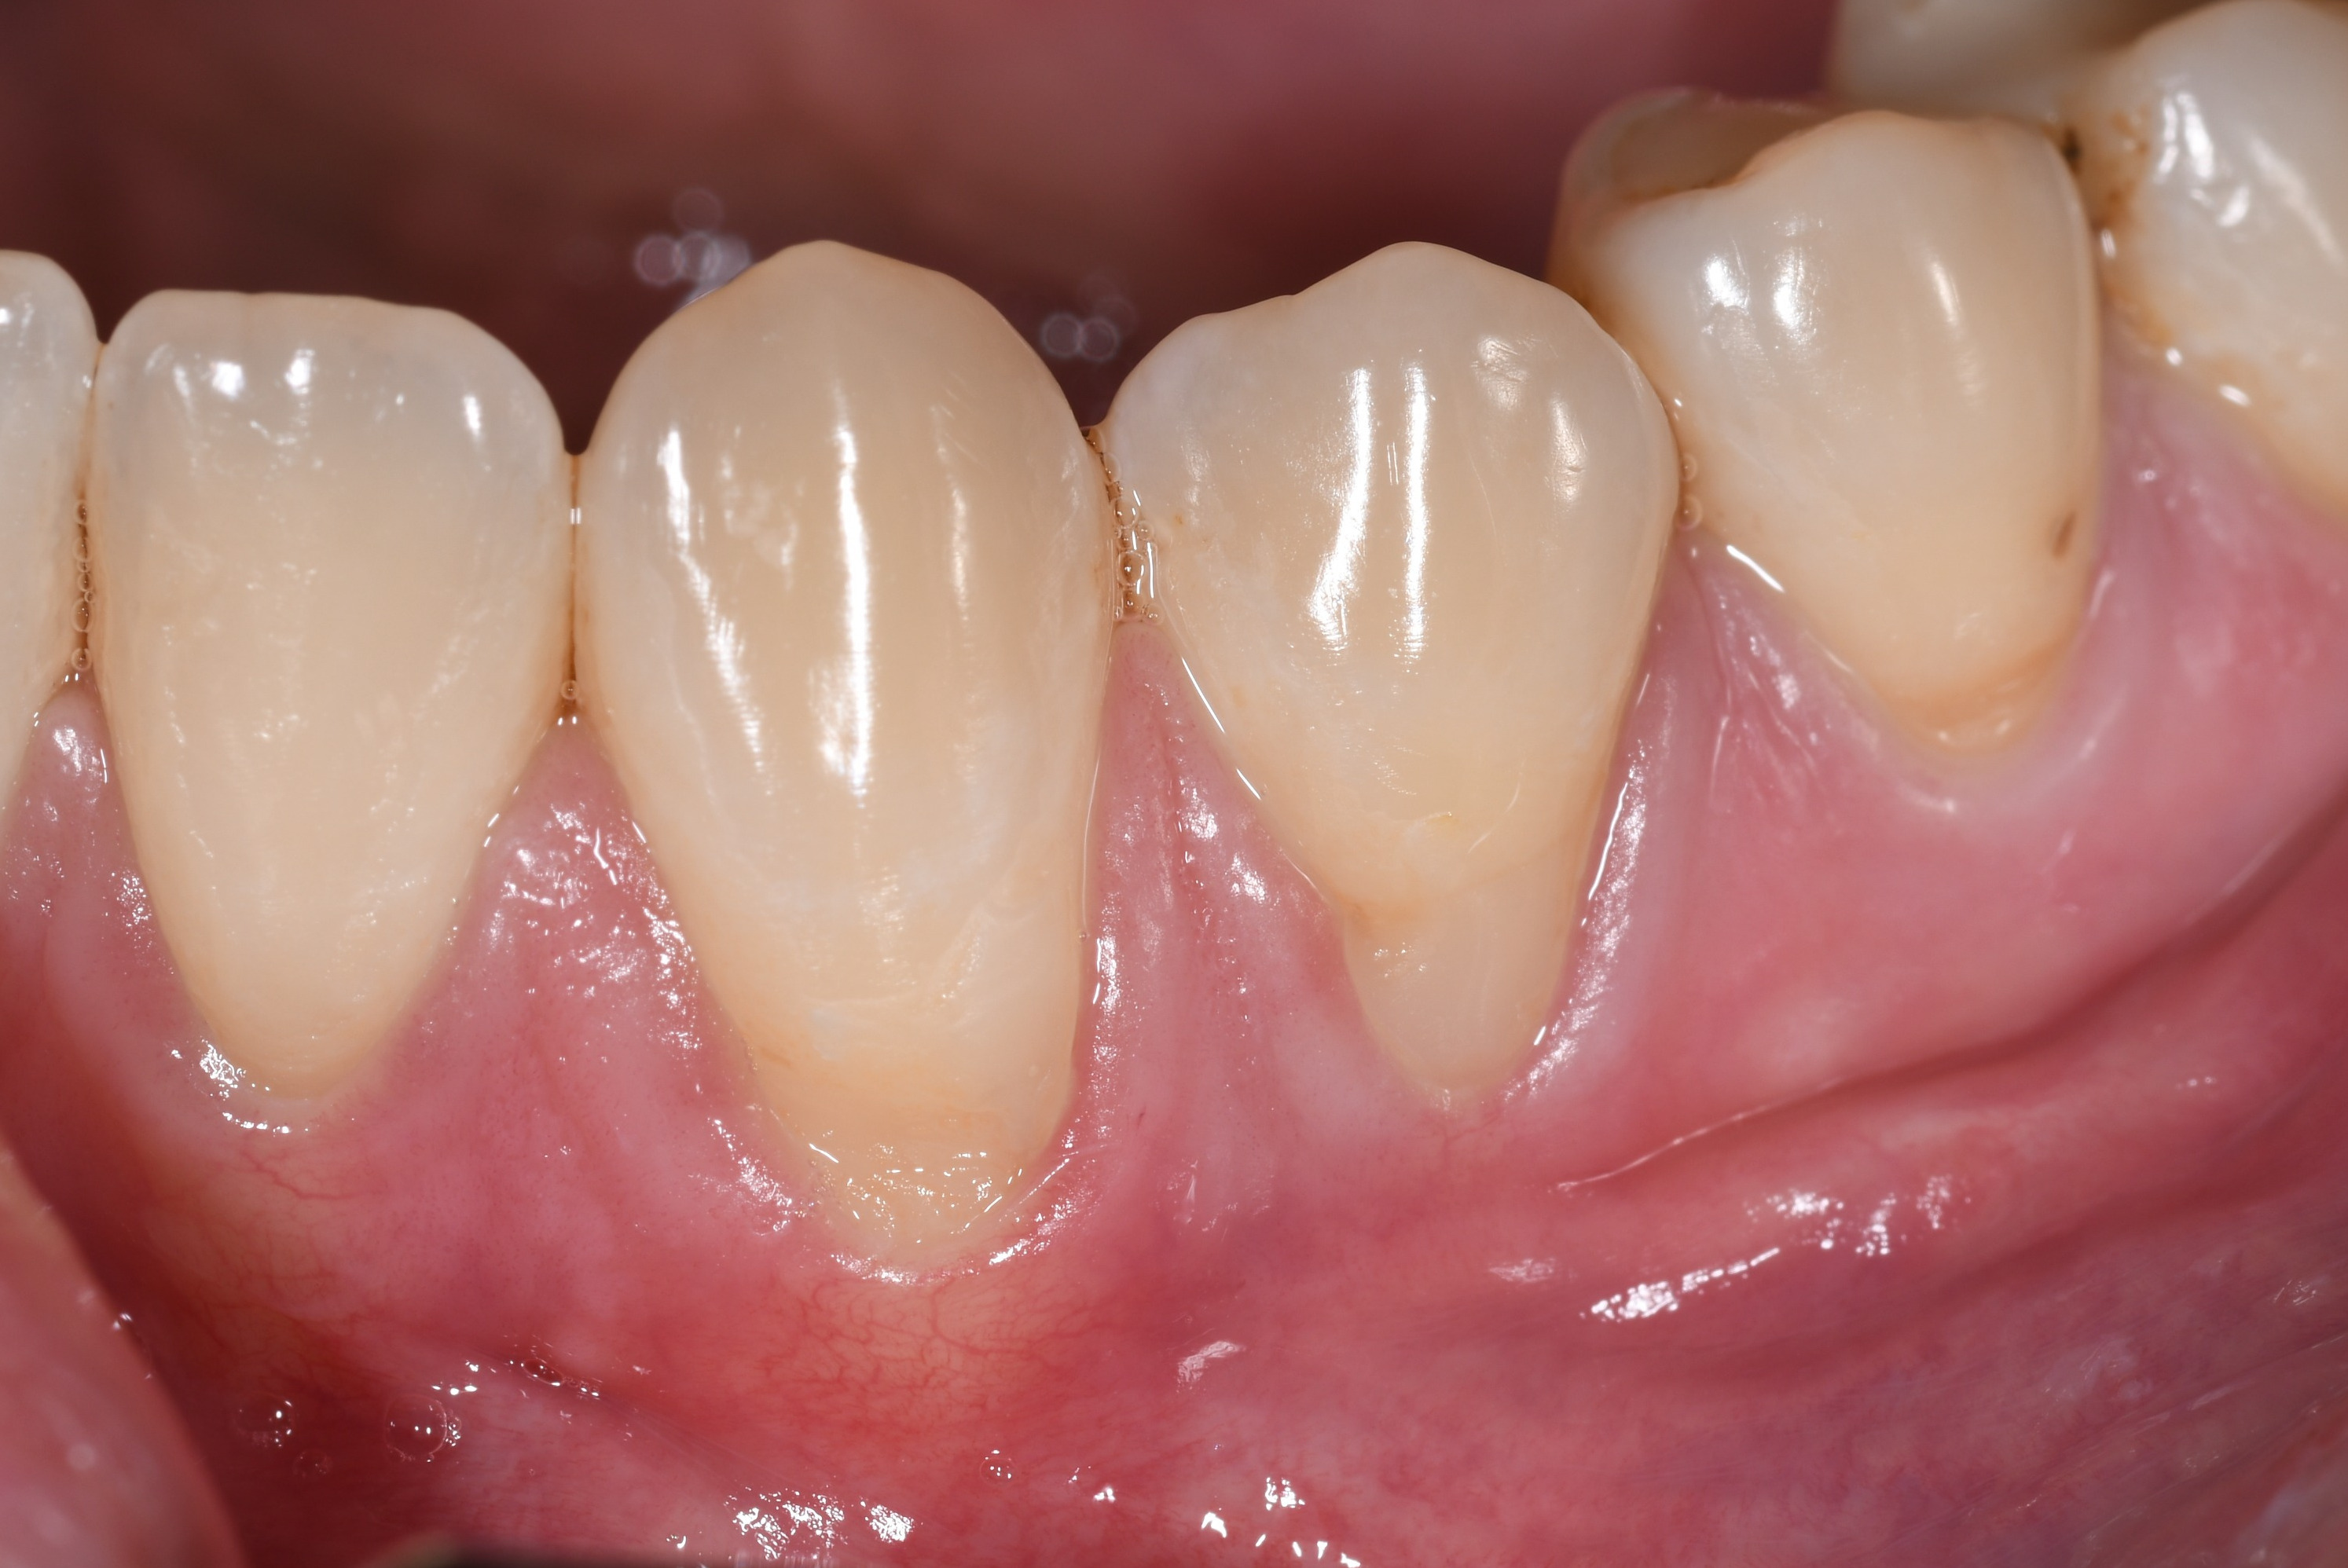

Prekrivanje recesija gingive spada u visoko specijalizirane mikrokirurške zahvate u parodontologiji.Osim samog prekrivanja recesije važna je i kvaliteta gingive oko zuba(pričvrsna gingiva). Predvidljivost rezultata nakon operacije ovisi o tipu i zahvaćenosti recesije.

Ovdje je prikaz slučaja operativnog zahvata recesije(Miller klasa 1) i situacija 2. godine nakon zahvata.